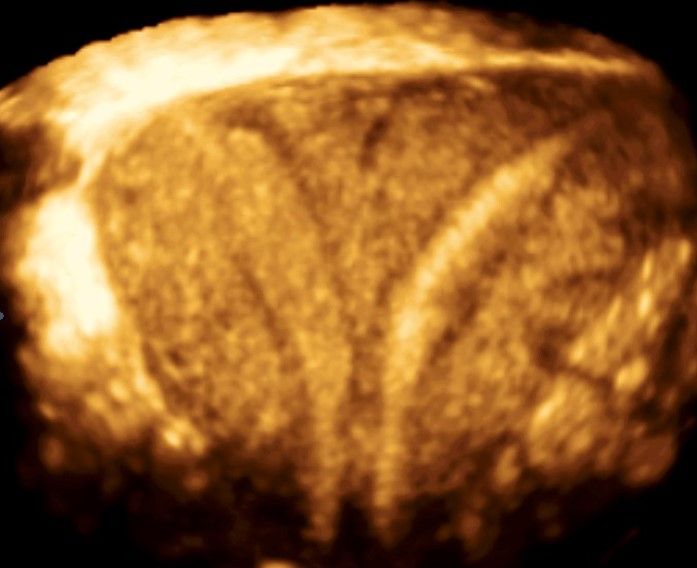

Современные экспертные УЗИ сканеры дают возможность проводить исследования всех органов в 3D. Это позволяет, используя полученный массив данных, получать диагностические сечения в любой плоскости, недоступной для обычного 2D УЗИ. Наиболее интересной является фронтальная. Например, визуализация полости матки. Диагностическая возможность выявления пороков развития превосходит все другие методы (рентгеновские и МРТ). Метод также позволяет уточнить положение ВМК (спирали) в полости матки, расположение миоматозных узлов, расположение плодного яйца на малых сроках, полипов. Сегодня современное экспертное ультразвуковое исследование невозможно без использования 3D УЗИ.